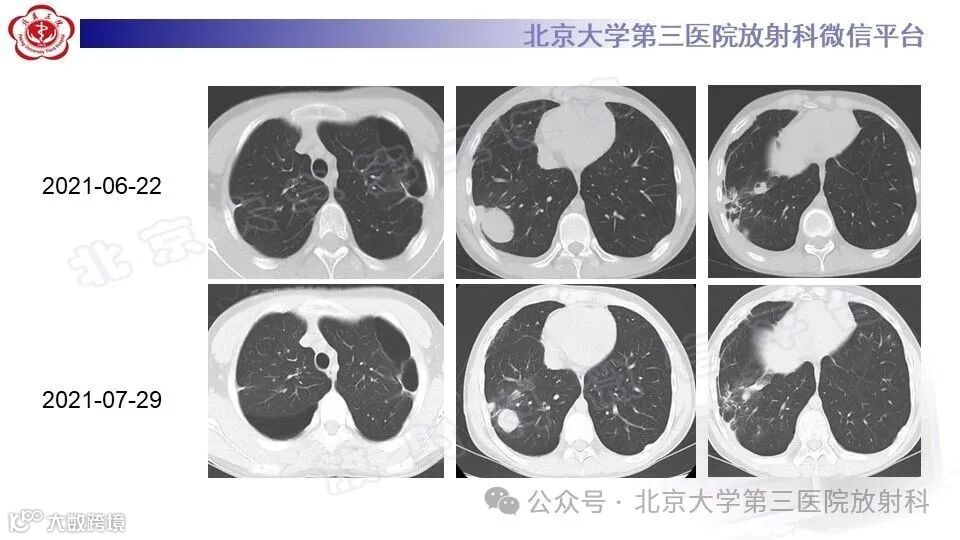

血管型Ehlers-Danlos综合征的胸部影像学改变